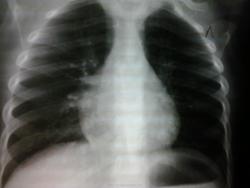

Лечится в стационаре с Ds:о.бронхит.Динамика положительная.Кашель редкий.На прямой рентгенограмме смущает треугольная тень в проекции правого корня(ателектаз?междол.плеврит?)Но на боковой не соответствует сегменту,гориз.плевре.Эта тень за грудиной? За счет чего ?

учитывая нечеткость фото,все таки видно,что стороны вашего треугольника образованы краями ребер,то есть наслоение теней

Но нижняя сторона не соответствует краю ребра

Как-то малоинформативно. Прямой переэкспонирован. А тень за грудиной ,возможно, за счет небольшого разворота. Есть впечатление, что утолщена тень плевры по ходу малой м/д щели, хотя повторюсь малоинформативно.

На боковом этой тени вообще нет. Мне кажется, это суммация теней, ребро и ортопроекции сосудов, частично сердца. Рисунок справа явно богаче. Ателектаз, тимус не вписываются.

Я бы расценила как субсегментарный ателектазик S3, контроль в динамике.

+1 Для средней дольки высоковато, а для S3 - в самый раз.) И главное слово - контроль - это святое.)

Всем спасибо!Я тоже на 1 место поставила ателектаз,только почему его не видно на боковой?Или все-таки это та небольшая тенюшка за грудиной?

За грудиной - то не она. Наша тенюшка ближе к корню идёт - пространственная ЗD-скиалогия её такова.)